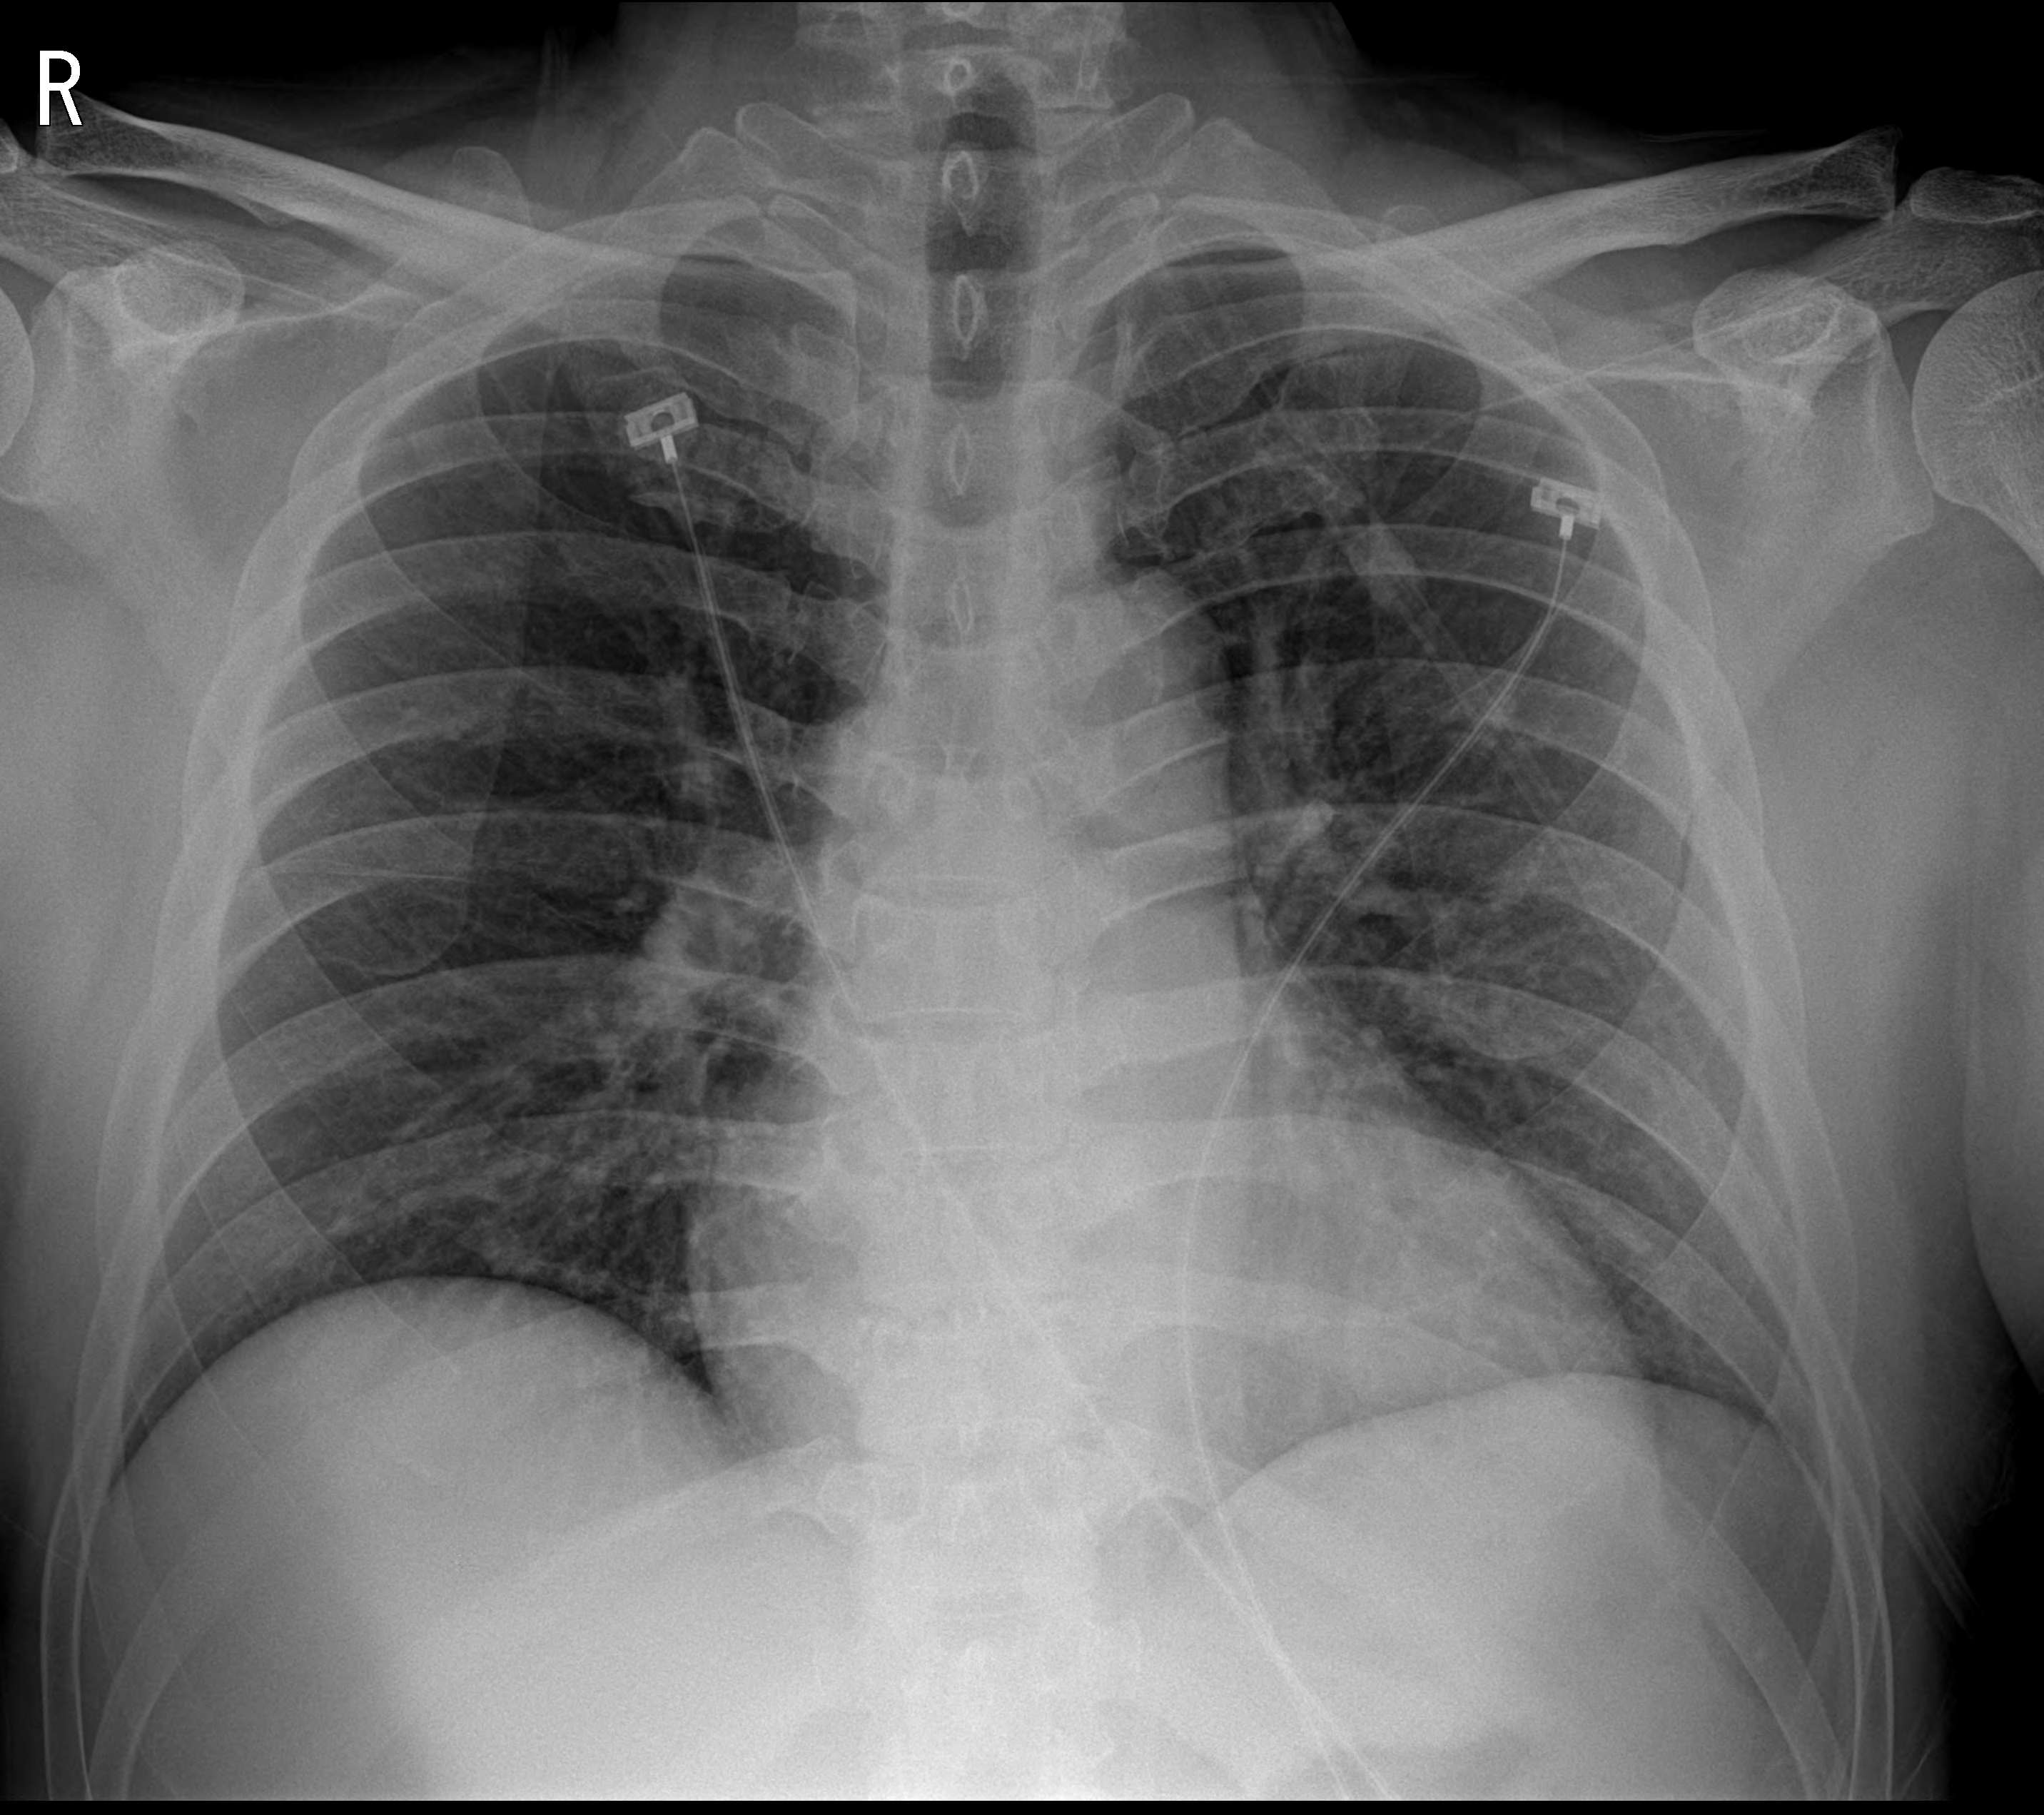

그사이 환자는 혈액검사 및 수액처치, 흉부 x ray 사진을 촬영하였다.